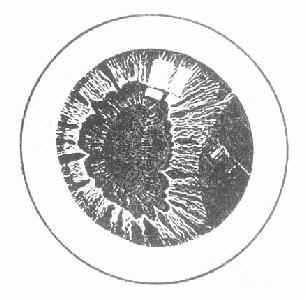

2.虹膜损伤与瞳孔异常 虹膜瞳孔缘及瞳孔括约肌断裂可造成瞳孔的不规则裂口。虹膜基质也可出现纵形裂口。严重挫伤可造成虹膜根部离断,虹膜根部有半月形缺损,瞳孔呈“D”字形),可出现单眼复视(图15-2)。有时整个虹膜从根部完全离断,形成外伤性无虹膜。瞳孔括约肌受损或支配神经麻痹,可造成外伤性瞳也扩大(外伤性散瞳),一般表现为中度扩大,瞳孔不园,对光反射迟钝或消失。睫状肌或支配神经受损时,常伴有调节麻痹,患者近视力出现障碍。

图15-2 虹膜根部离断